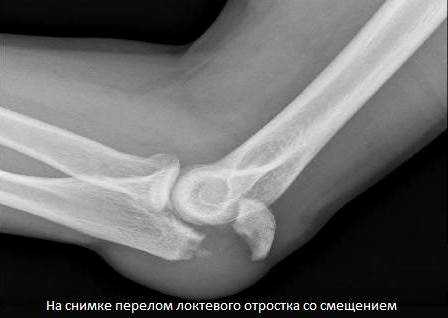

Перелом локтевого отростка локтевой кости. Рентгенограмма в боковой проекции.